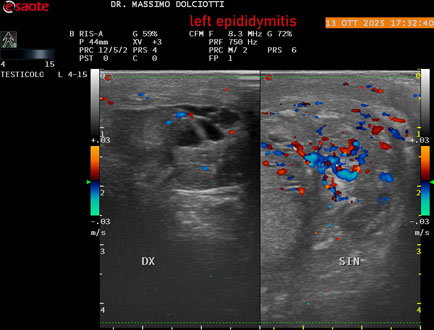

Data inserimento: 14/10/2025

Ecografia del: 13/10/2025

Strumento: Esaote MyLab Eight

Sonda: Lineare Multifrequenza 4-15 MHz

Età Paziente: M 70 anni

Motivazione dell'esame: da 2 giorni dolore al testicolo sinistro.

Commento all'esame: le immagini ed il video documentano l'epididimo sinistro spiccatamente aumentato di volume e di vascolarizzazione, come da flogosi. Didimo sinistro lievemente aumentato di volume. Quadro clinico ed ecografico da ricondurre ad epididimite acuta sinistra.

Conclusioni: epididimite acuta sinistra (acute left epididymitis).

Presentazione: Dr. Massimo Dolciotti - Ancona